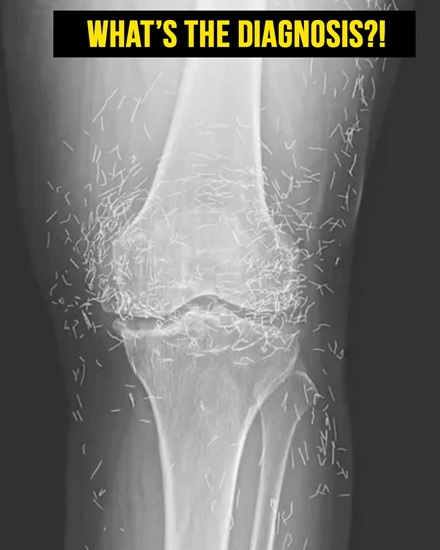

Medical Experts Uncover Surprising Find in Woman’s Knees

A 65-year-old woman from South Korea sought help for chronic knee pain, expecting routine care for osteoarthritis. Doctors, however, discovered something unusual that immediately drew attention and became a remarkable medical case. Osteoarthritis slowly wears down the cartilage in joints, causing pain, stiffness, and swelling. Daily activities like walking short distances, bending, or climbing stairs become increasingly difficult and exhausting for those living with the condition. For years, she relied on standard pain medications and… CONTINUE READING…